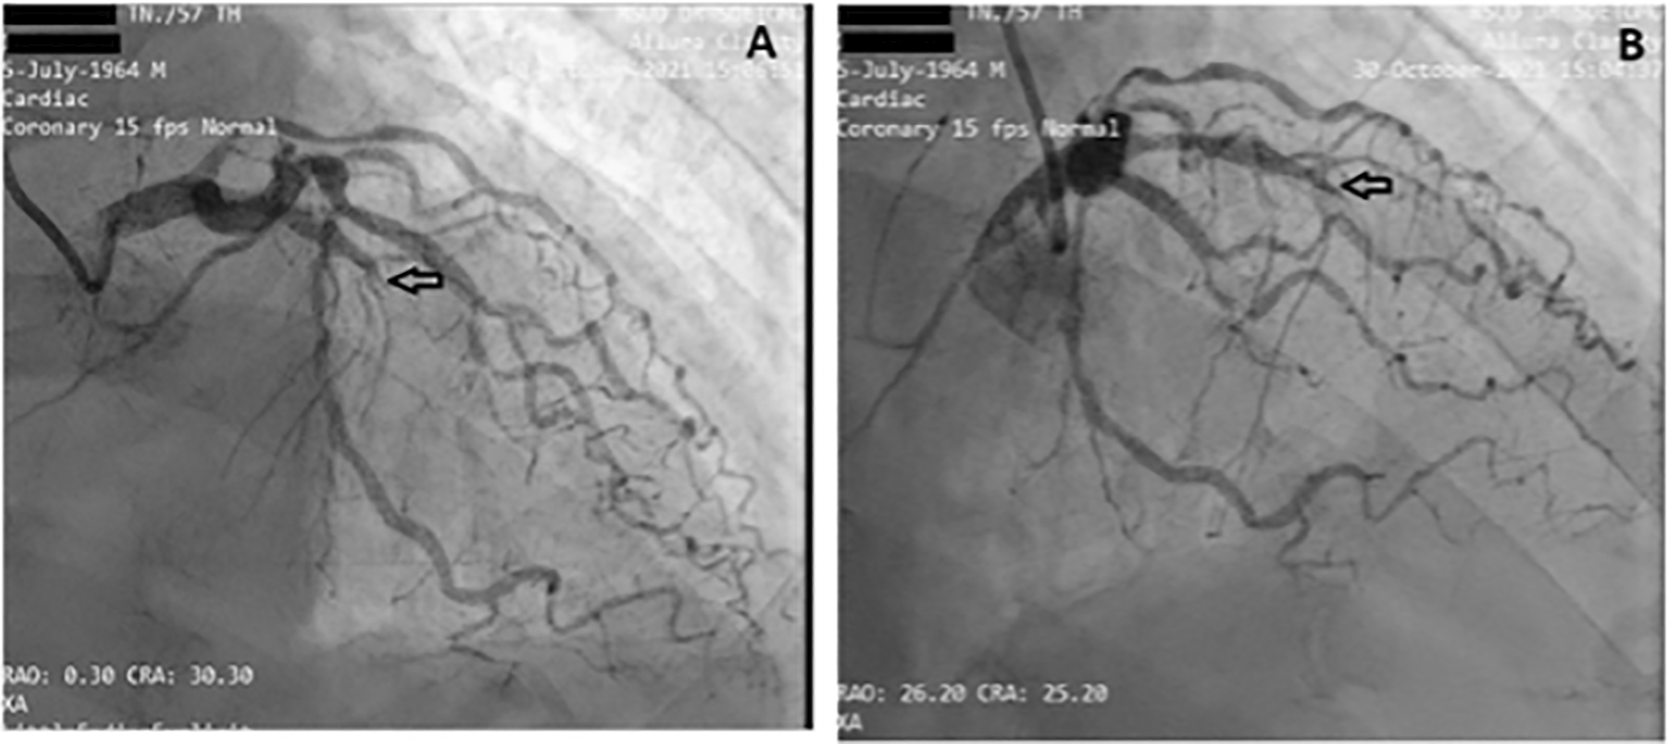

Before the invasive strategy was done, the patient had another electrocardiography eight hours after the first electrocardiogram, based on the second (Figure 2). The electrocardiogram showed ST-segment elevation changes that were greater than 1 mm. The early invasive strategy (Figure 3 and Figure 4; Extended data: Video 1 and Video 2)3,4 showed that the left anterior descending artery (LAD) had a critical occlusion of 99% in the middle of left anterior descendants coronary artery (Figure 3). The left circumflex artery (LCx) had non-significant stenosis of 40% proximal and 65% distal, and right coronary artery (RCA) had non-significant stenosis of 55% distal. The RCA had grade 2 collateral arteries that supply blood to the middle of left anterior descendants coronary artery (Figure 4).

The left circumflex artery (LCx) had non-significant stenosis of 40% proximal and 65% distal LCx.